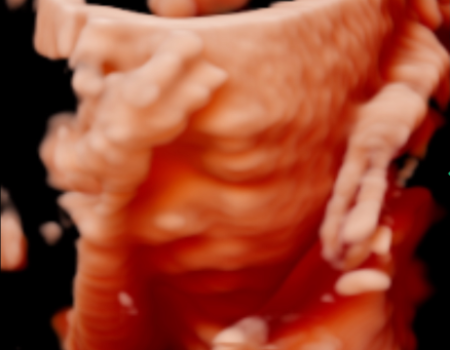

¡La ecografía 5D es una imagen en tres dimensiones y en tiempo real, como la 4D, pero en la que el tratamiento de las imágenes en el ordenador permite suavizar las texturas, modificar el color de la imagen y aplicar un foco de luz desde diferentes ángulos de forma que se crean luces y sombras y esto le da una imagen más real.

La Ecografía 5D incorpora un procesamiento más avanzado que optimiza la iluminación, la textura y la profundidad de la imagen, logrando una representación más clara y uniforme del bebé. Gracias a estos ajustes, los rasgos faciales y los movimientos se aprecian con mayor naturalidad, reduciendo imperfecciones visuales propias de otras modalidades y ofreciendo una imagen final más definida y comprensible para las familias.